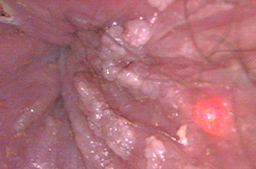

Lesiones por vph en región peri anal y ano en forma de condilomas acuminados.